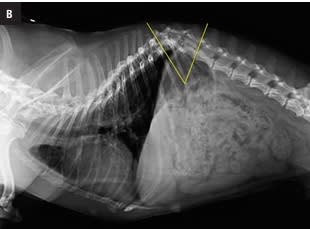

Este atlas de consulta rápida ayudará al clí­nico a obtener la máxima información de sus estudios radiográficos del tórax. Presenta gran cantidad de imágenes que guiarán al veterinario en su interpretación radiográfica, desde la misma técnica, la posición más idónea según la patologí­a que se sospeche o el estado clí­nico del paciente, o variaciones fisiológicas, hasta el órgano o estructuras torácicas a evaluar. Presenta montajes anatómico-radiográficos para ayudar a visualizar las estructuras que se están valorando en la radiografí­a. Aporta imágenes de las proyecciones radiográficas torácicas normales de más de 30 razas caninas para su comparación directa lo que hacen de este libro una guí­a de referencia de radiografí­as torácicas raciales.